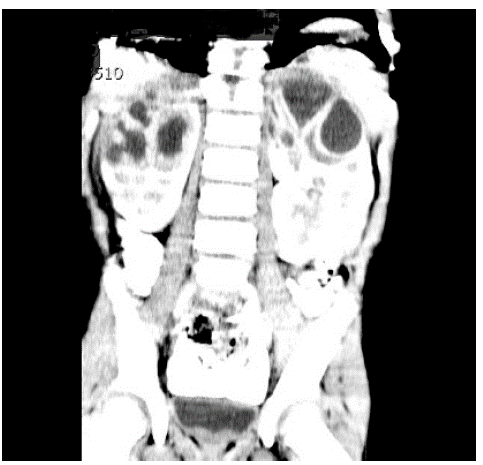

Al inicio, no se solicitaron estudios de imágenes renales mientras se analizaban los tomados en las ITU previas. A las 48 horas de manejo, el paciente persistía con picos febriles, por lo que se decidió llevar a cabo otros estudios complementarios como función renal, cuyo resultado estuvo dentro de límites normales, y una ecografía renal y de vías urinarias que reportó una imagen sugestiva de pielonefritis bilateral de los polos superiores sin poder descartar presencia de abscesos incipientes. Se dispuso continuar con la administración del mismo antibiótico hasta tener el reporte de urocultivo y solicitar una escanografía de abdomen (Figura 1), que reveló lesiones focales hipodensas que comprometen las pirámides de ambos lóbulos superiores de los riñones, las cuales podían relacionarse con proceso infeccioso.

TC Abscesos renales.

Figura 1: TC Abscesos renales.

Fuente: Documento obtenido durante la realización del estudio.